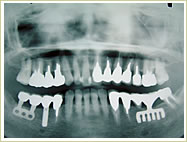

症例 68歳 女性 インプラント埋入数:1個 9本 画像拡大

治療前 治療後